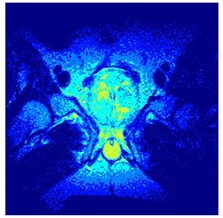

In this subsection, we will discuss the experiment designed to evaluate the performance of EO with cross-entropy for the segmentation of prostate MRI images. To this end, we use a group of reference images formed by a set of six prostate MRI images; see Figure 4. All the images from the group were extracted from the Ferenc Jolesz National Center for Image-Guided Therapy, Harvard Medical School, or Brigham Health Hospital datasets with no additional preprocessing [50]. Prostate MRI images are primarily used for disease diagnosis or to establish treatment for prostate-related diseases such as prostatitis, benign prostatic hyperplasia (BPH), and prostate cancer, among other diseases or medical conditions. In the context of this article, the images were used to test the efficiency of the equilibrium optimizing algorithm and compare it with the other six chosen algorithms. The segmentation of MRIs is carried out over four different thresholds levels: = 3, 4, 5, and 8. Due to the nature of the images, there was a limited number of different tissues in the images; thus, there was no point in evaluating a larger number of .

Figure 4.

Eleven transaxial-cut prostate MRI images. This figure presents a set of eleven transaxial-cut magnetic resonance (MR) images of the prostate. These images serve as the input dataset for evaluating the segmentation performance of the proposed algorithm.

Table 5 presents the segmentation of the MRIs using EO for a qualitative inspection. From Figure 5, it is clear that two lumps in the prostate have been highlighted by the thresholding process. Prostatic MRIs present noisy conditions, which makes it difficult to visualize the thresholding with the naked eye, so in Figure 5 we present the thresholded image as well as the histogram with the values of the thresholds generated by the EO. It can be observed in the histogram that the thresholds present an adequate distribution, even though this particular image has impulsive noise and a simple shape. Our findings indicate that four thresholds are typically sufficient for this application, which corresponds to identifying five different tissue types in the image. A smaller threshold value may result in a lack of sufficient contrast to highlight relevant anatomical structures, such as the prostate capsule. In contrast, a higher number of thresholds may lead to the incorrect differentiation of anatomical regions that should be connected.

Table 5.

Segmentation of transaxial-cut prostate MRI images Using EO and cross-entropy. This table presents the segmentation results of transaxial-cut prostate MRI images using the equilibrium optimizer (EO) and cross-entropy. Each row corresponds to a distinct MRI image, while the columns nt represent the number of thresholds applied during segmentation. The results illustrate the performance of the EO algorithm across different threshold levels for each image.